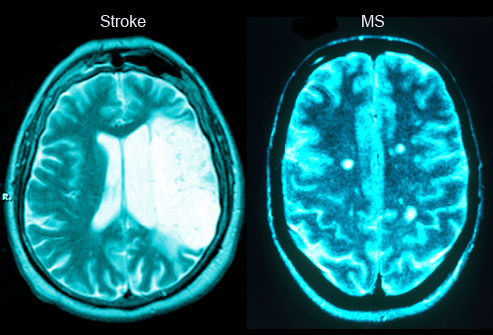

Η σύγχυση, οι δυσκολίες στην άρθρωση και η μυϊκή αδυναμία είναι τρία κοινά συμπτώματα που εκδηλώνονται. Η ξαφνική εμφάνιση τους ομως μπορεί να υποδηλώνει πιθανό εγκεφαλικό επεισόδιο.